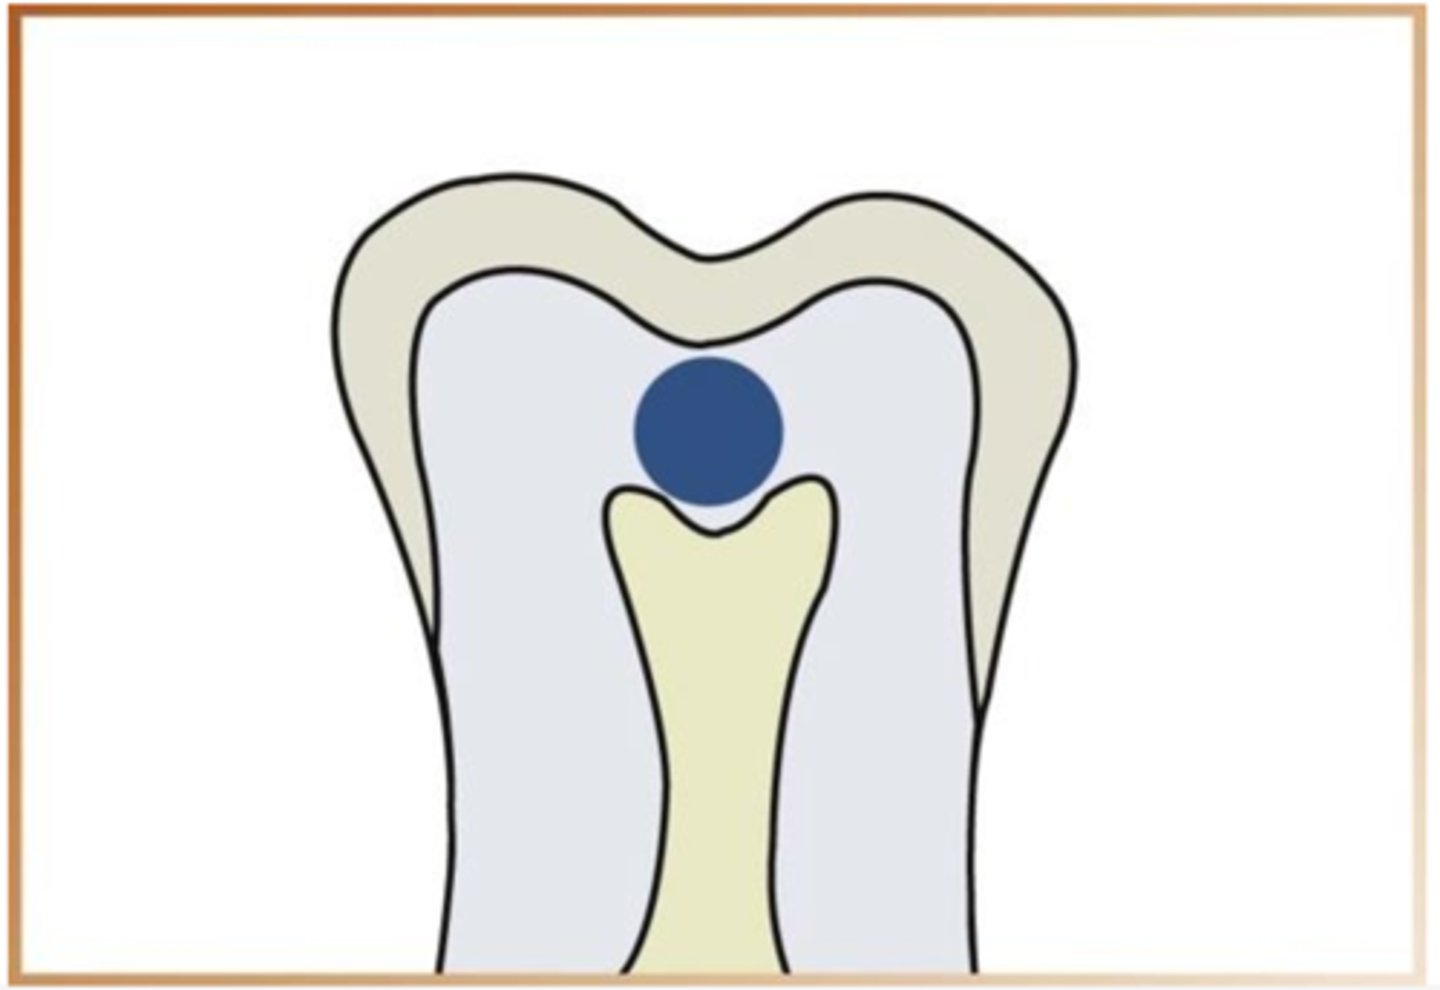

can you detect buccal and lingual caries on a radiograph

difficult to detect on radiograph due to location but appear as a circular radiolucent area